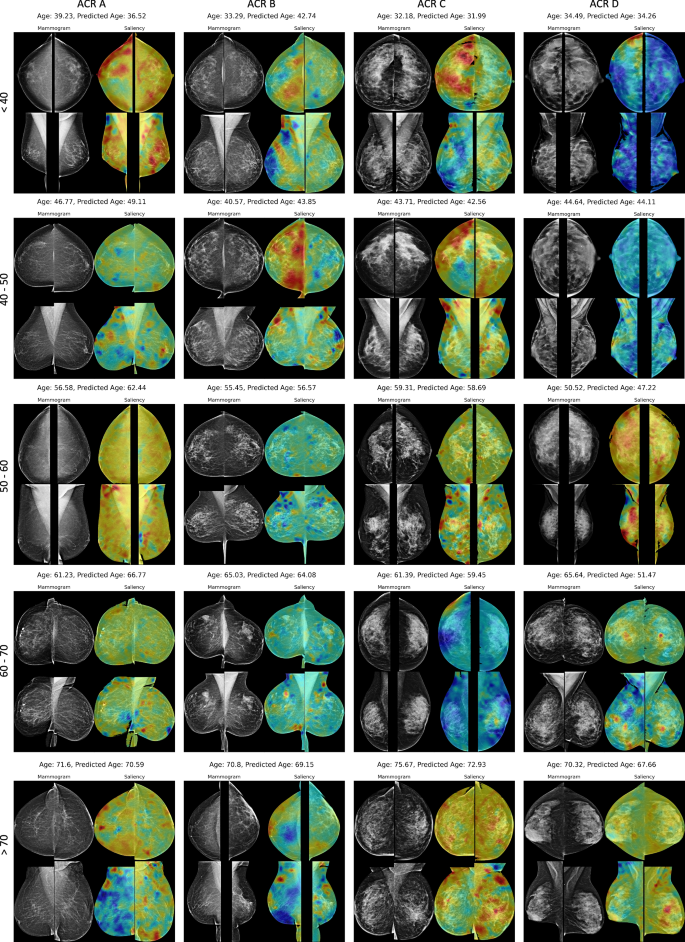

For model interpretability, we estimated saliency maps through occlusion sensitivity analysis19. Specifically, we utilized different-sized masks (32 × 32, 64 × 64, 128 × 128, and 256 × 256) to occlude parts of the breast areas in the input images by setting the corresponding areas to black images. Age-specific saliency maps were computed by categorizing the data into five sub-age groups, delineated by 10-year intervals, ranging from ≤40 to ≥70 years, and into four density groups (A-D) based on ACR density classification for mammograms. Results in Fig. 4 show that the MLO views provide more aging-related informative features compared to the CC views. Our proposed Mammo-AGE model commonly focuses on breast skin thickness, fibroglandular breast tissue, calcifications, masses, and breast vessels. Importantly, as shown in Supplementary Fig. 9, the model could learn the consistent inherent aging pattern features for each woman over time. To accurately model natural biological breast tissue aging changes, we trained the model only on the healthy population. This means that unseen abnormal tissue may lead to higher deviations in age estimation for the model. We further analyzed saliency maps from time-point mammograms of patients who later developed breast cancer. We observed high-deviation areas (blue color) in focal fibroglandular regions and structural asymmetry between views, suggesting an abnormal aging pattern associated with breast cancer risk.

4-view (bilateral CC and MLO) mammograms from the inhouse dataset are shown. Saliency maps highlight regions that the model focuses on when predicting breast age. Age-specific saliency maps were computed by categorizing the data into five sub-age groups, delineated by 10-year intervals, ranging from ≤40 to ≥70 years, and into four density groups (A–D) based on ACR density classification for mammograms. Within each subgroup, different-sized masks (32 × 32, 64 × 64, 128 × 128, and 256 × 256) were used for the analysis. Normalization was carried out by dividing the entire image by the maximum value, ensuring that the values of the final saliency map ranged from 0 to 1. The minimum value within this range corresponds to blue color on the colorimetric map, while the maximum value corresponds to red. The saliency maps reveal that the model commonly focuses on features such as breast skin thickness, fibroglandular tissue, calcifications, masses, and breast vessels. The MLO views generally provide more informative features related to aging compared to the CC views.